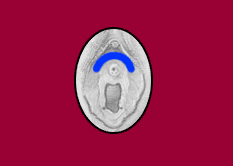

U-punktet er et punkt alle kvinder har, det er et meget følsomt område, fyldt med nerver. Området befinder sig over og på hver side af urinrørs åbningen.

Det er ikke et punkt der vokser ligesom G punktet, men er en stor koncentration af nerver. Stimuleres U punktet rigtigt, vokser en skøn varm lyst følelse op i hendes mave og ud i hendes ben. Det er også muligt at give en kvinde en U punkts orgasme, da virker punktet lidt ligesom klitoris.. Men det er kombinationen af flere punkter, der giver de meget intense oplevelser. Stimulering af A punktet, G punktet, klitoris, X punktet, ja alt hvad der får hende tændt, bliver bedre i kombination med U punktet.